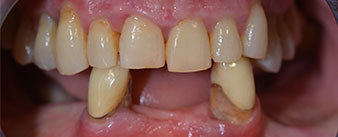

The necessary periodontal treatment and extraction in the maxilla was to be performed at a later point in time, as the patient is a teacher and was busy with school leaving exams at the time. She could neither eat nor speak properly, as the temporary prosthesis was very fragile, breaking regularly and under the slightest strain.

Following an explanation of the various treatment options open to her, the patient decided on extraction of the residual dentition in the mandible, an immediate implantation and treatment with the Fast & Fixed method (bredent medical), whereby the provisional fixed denture is screwed onto four implants on the same day as the surgery. The goal was to operate on the patient on the Friday so that she could assist in the oral examinations on the following Monday.